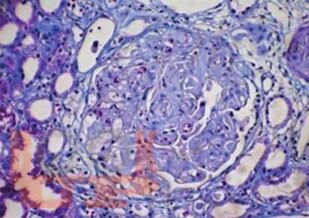

В монографии обобщены результаты исследований авторов и современные литературные данные, посвященные тромботической микроангиопатии у пациентов, находящихся в листе ожидания трансплантации почки, и у реципиентов ренального трансплантата. Большое внимание уделяется патогенетическим механизмам, классификации, проблемам профилактики, ранней диагностики и лечения тромботической микроангиопатии после трансплантации почки, а также влиянию данного осложнения на ближайшие и отдаленные результаты трансплантации.